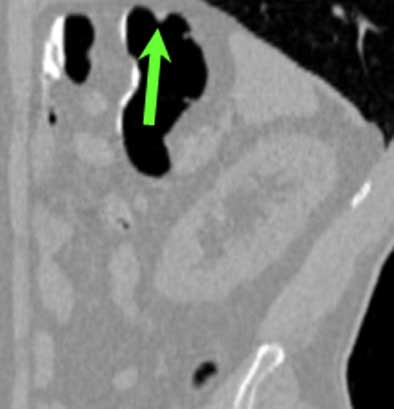

| Top to bottom: A 10-mm polyp in the splenic flexure can be seen in axial, sagittal, coronal, and 3D views. All images courtesy of Dr. Riccardo Iannaccone, University of Rome "La Sapienza." |

Per patient, virtual colonoscopy yielded an average sensitivity of 89.9% (95% CI, 90.9%-96%), average positive predictive value of 88% (95% CI, 83.3%-91.5%), and average negative predictive value of 93.5% (95% CI, 90.9%-96%), the authors wrote. In the more rigorous per-polyp analysis, VC's overall sensitivity was 64.4% (95% CI, 60.2%-68.7%; 72% for neoplastic polyps), including 95.5% sensitivity for polyps ≥ 8 mm (95% CI 92.1%-99%; 100% for neoplastic polyps), and 86% for polyps ≥ 6 mm (95% CI, 81.7%-90.5%).

Virtual colonoscopy produced 16, 16, and 21 false-positives for each of three readers, most due to the presence of thickened folds, and surprisingly in the prep-free study, few false-positives (4, 4, and 5, respectively) were due to fecal material. "This result is correlated to the fact that the use of an effective fecal tagging strategy in our study helped the readers in the differentiation between fecal material and colonic polyps," the authors wrote.

There were also 54, 57, and 52 false-negatives at VC, with no clear cause determined for 59, 51, and 53 of them, even in retrospective analysis. These may have been due to the limits of spatial resolution in the image data, but most of the lesions carried a very low likelihood of malignancy, the group noted. Interobserver agreement between the three readers was high both per-polyp (k = 0.61-0.64) and per patient (k = 0.79-0.91).